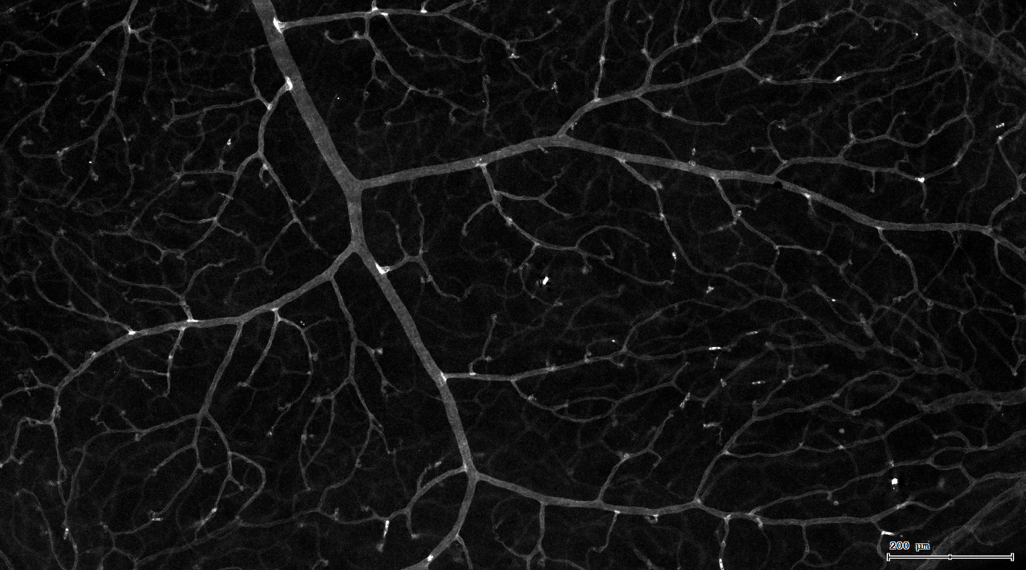

5. 识别血管的Texa Red染色区域面积及强度。

7. 根据毛细血管亮斑的识别结果,统计新生小血管数量。

血管识别:根据Texa Red通道进行识别,并去除面积小的及非同一焦面的血管,仅对确定的清晰的同一焦面的大血管进行面积统计。